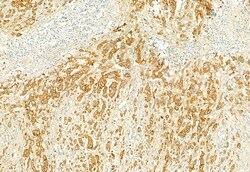

PLCE1 Polyclonal Antibody, Invitrogen™

Antibody detects endogenous levels of total PLCE1.

This gene encodes a phospholipase enzyme that catalyzes the hydrolysis of phosphatidylinositol-4,5-bisphosphate to generate two second messengers: inositol 1,4,5-triphosphate (IP3) and diacylglycerol (DAG). These second messengers subsequently regulate various processes affecting cell growth, differentiation, and gene expression. This enzyme is regulated by small monomeric GTPases of the Ras and Rho families and by heterotrimeric G proteins. In addition to its phospholipase C catalytic activity, this enzyme has an N-terminal domain with guanine nucleotide exchange (GEF) activity. Mutations in this gene cause early-onset nephrotic syndrome; characterized by proteinuria, edema, and diffuse mesangial sclerosis or focal and segmental glomerulosclerosis. Alternative splicing results in multiple transcript variants encoding distinct isoforms.

| Immunocytochemistry, Immunohistochemistry (Paraffin), Western Blot | |

| A synthesized peptide derived from human PLCE1(Accession Q9P212), corresponding to amino acid residues R2267-Q2302. | |

| Human, Mouse, Non-human Primate, Rat | |